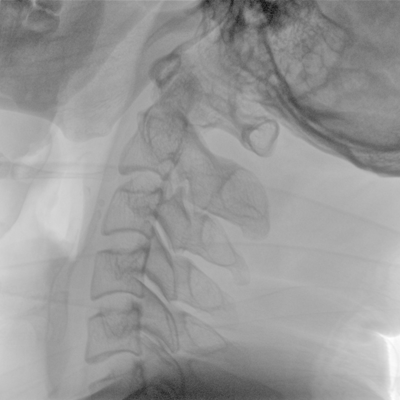

可用于常規(guī)的外周血管介入手術(shù),設(shè)備的移動性好,對手術(shù)室空間要求低,可滿足長時間X光透視的需求,且增加了獨特的血管影像處理功能,是開展介入手術(shù)的理想設(shè)備。

優(yōu)質(zhì)平板探測器、可靈活升降調(diào)節(jié)SID、獨特圖像處理系統(tǒng)、高品質(zhì)濾線柵,大視野成像清晰不失真。

采用電動機架設(shè)計,可以實現(xiàn)C形臂繞水平軸旋轉(zhuǎn)、沿弧滑動、上下升降、 水平延伸四方向電動運動,充分滿足臨床擺位需求。